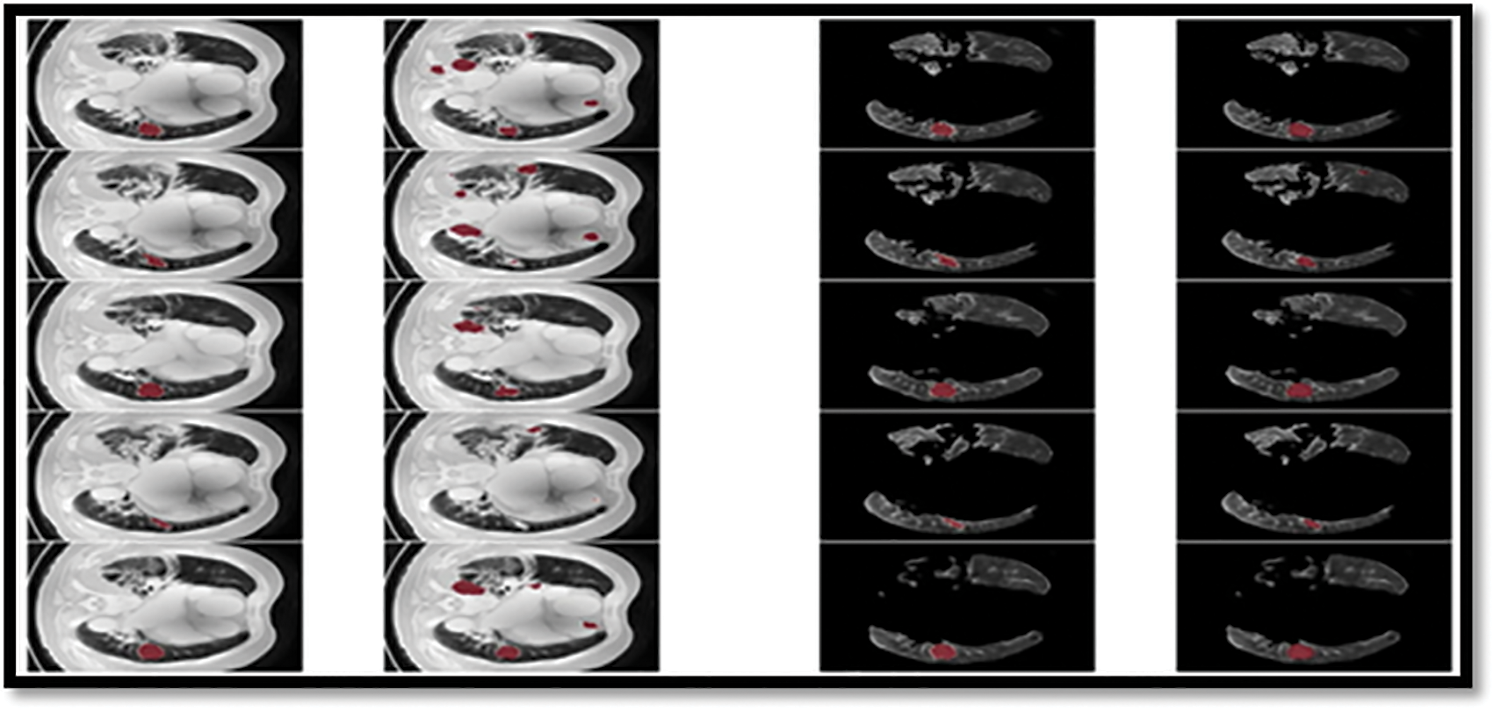

This research examines data from a variety of sources and includes 472 and 50 occurrences, respectively. Complementary labeling and pre-processing, as demonstrated in Tables 4–6, outperform mono input in the majority of cases. On the other hand, complementary labeling is ineffective in the absence of pre-processing. When dealing with little amounts of data, complementary labeling may be quite beneficial. As a result, this research examines the viability of labeling enhancement. Hybrid negatives are preferred over mono-input positives because smaller data volumes are more sensitive to hybrid negatives. Positive mono outputs provide a value of 90%, whereas negative hybrid inputs produce a value of 92% and the output of the results can be seen in Fig. 9. If the data set is insufficient, more labels may be necessary to round.

Figure 9: The ground truth prediction before segmentation and after segmentation

From the Table 8, it was clearly evident that our method was performed very well with few samples size from LUNA 16 dataset. The results clearly shows that out proposed model and method are good at classifying odd benign and Malignant tumours. As, a result the model has achieved a trust gain when compared with various others methods and clear output was shown in Fig. 10.

Figure 10: Showing the proposed classifier on LuNa-16 dataset. Second column showing the original image, third column showing the Lung Lode, and last two is the segmented image